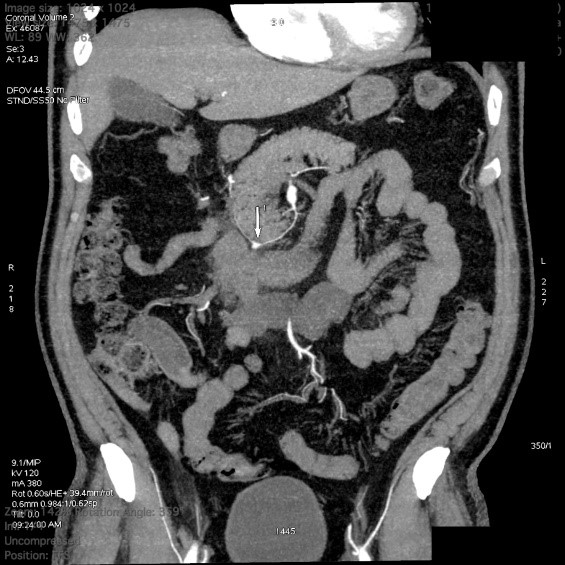

На амбулаторном этапе обратился в «Адамант Медицинская Клиника», где на протяжении последних лет проходит диспансерное наблюдение. Учитывая, что источник кровотечения не был установлен, было принято решение выполнить ангио-МСКТ брюшного отдела аорты и ее ветвей, что и выполнено 25.08.2021 г., по результатам которого выявлена аневризма нижней панкреатодуоденальной артерии. С целью уточнения диагноза рекомендовано выполнение ангиографии аорты и артерий брюшной полости, с последующим решением вопроса о необходимости оперативного лечения (эмболизации) (рис. 1, 2).

Рис. 1. МСКТ-ангиография брюшной аорты и ее ветвей.

Fig. 1. MSCT angiography of the abdominal aorta and its branches.